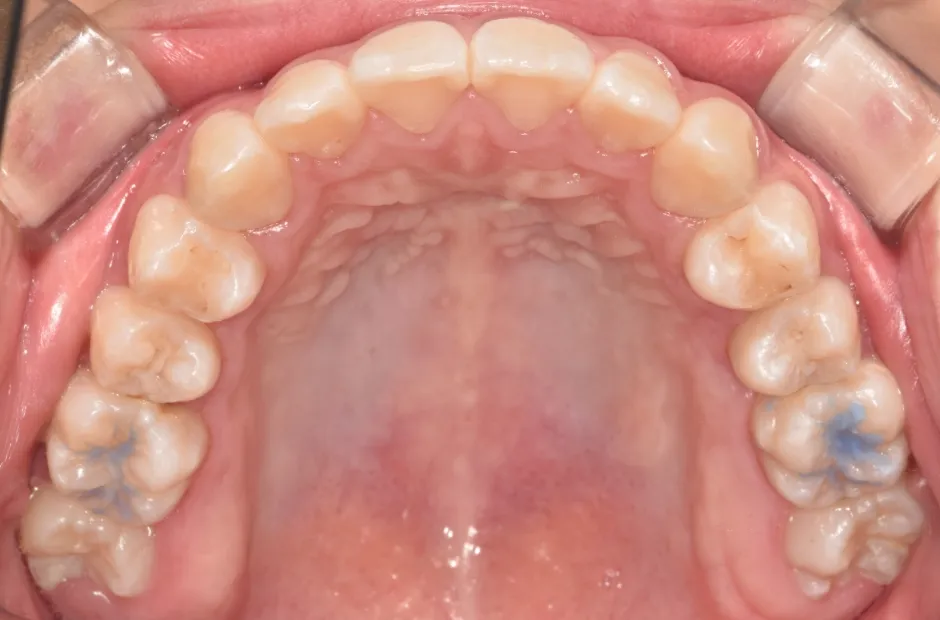

治療症例

ブラケット矯正

前歯部反対咬合

| 診断名・主訴 | 前歯部反対咬合 |

|---|---|

| 年齢・性別 | 14歳・男性 |

| 治療期間・回数 | 1年2か月 |

| 治療に用いた主な装置 | ブラケット矯正 |

| 抜歯部位 | なし |

| 治療費 | 60万円(税抜) |

| リスク・副作用 | 装置による違和感・疼痛・歯肉退縮・歯根吸収・虫歯のリスクなど |

治療前

治療中

治療後